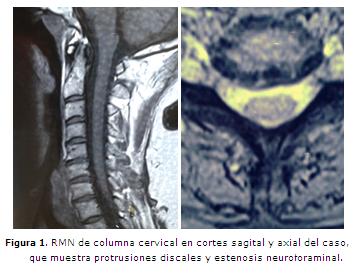

Mujer de 59 años, con cervicobraquialgia intensa, 9/10 de la escala verbal numérica (EVN), afectando territorio de raíces nerviosas C6 y C7, con impotencia funcional y sin alteraciones sensitivas. Una resonancia magnética nuclear (RMN) de columna cervical mostró protrusiones discales circunferenciales a nivel de C5-C6 y de C7-T1. La figura 1 muestra las imágenes correspondientes al estudio señalado, en cortes sagital y axial.